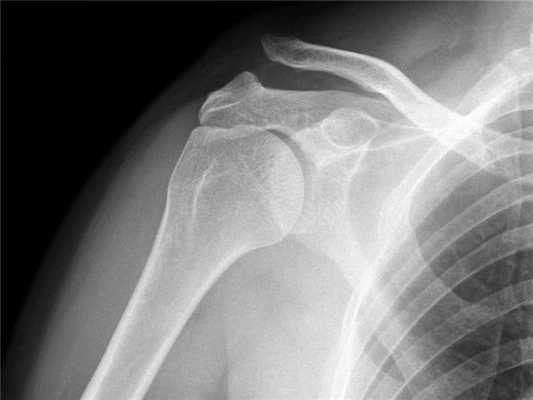

Практически во всех случаях определить получение вывиха ключицы оказывается достаточно легко, с учетом проявляемых клинических признаков. Из дополнительных методов исследования больному может быть назначено проведение рентгеновского исследования. Для правильного установления диагноза, целесообразно выполнять рентгенограмму здорового и больного плеча на одной пленке.

Для подстверждения диагноза выполняется рентгенография плечевого сустава. На рентгенограмме четко видно, если произошел вывих акромиального конца ключицы.

Диагноз вывиха акромиального конца ключицы

Диагноз вывиха акромиального конца ключицы иногда очень прост и все очевидно при осмотре, а иногда приходится решать целую головоломку. Наиболее оптимальным и распространенным способом диагностики является рентгенография. Стоит сказать, что, как не бывает одинаковых людей, так и не бывает одинаковых ключиц. Чаще всего причиной ложного диагноза индивидуальные особенности акромиально-ключичного сустава.

Поэтому целесообразно выполнять рентгенограмму не одного плеча, а двух сразу - что позволит оценить нормальное строение противоположной ключицы.

В сомнительных случаях иногда выполняют функциональную рентгенографию - в руку берут груз, который оттягивает ее вниз и вывих становится более очевидным.